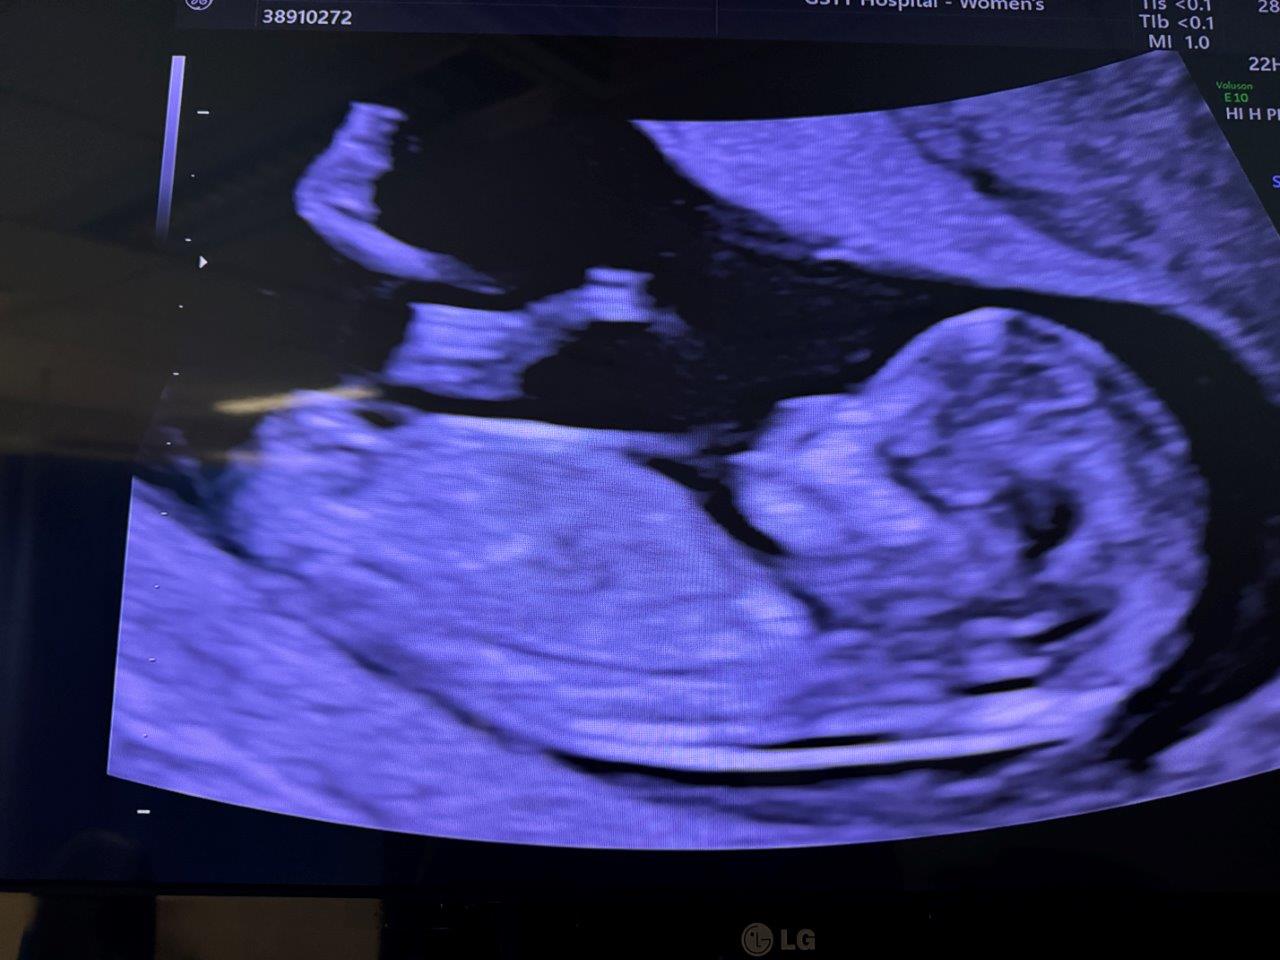

A few photos of other adventures throughout 2024. The biggest being sharing the great news that Keoni is pregnant and seeing the joy from family and friends. Some coast hangs, a sneaky long weekend in Crete, catching up with friends and family but all in all a relatively quiet back end of the year post South America as the pregnancy moved further and further along.